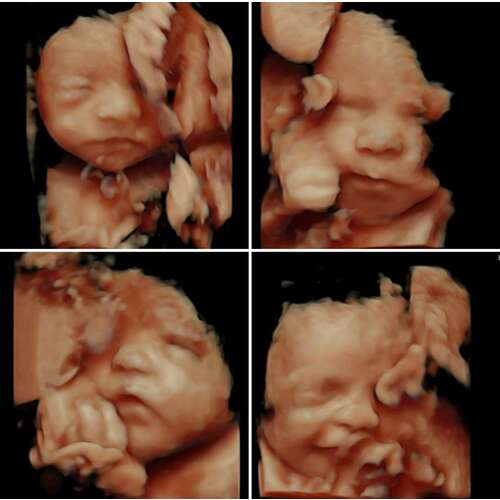

Wij hebben overigens van de twee oudsten echt wel mooie plaatjes en filmpjes. Sommige foto’s zijn zo duidelijk dat je na de geboorte en (ver) daarna nog steeds ‘herkenning’ ziet. Zo hebben mijn zoon en dochter nog steeds zo nu en dan het ‘bekkie’ als op de echo

Bij mij had ze hem de eerste keer met 23 weken onverenigbaar aangezet. Super vroeg, maar de kleine was groot en vol waardoor de echo mooi was.

Uiteindelijk een betaald 3D/4D gedaan met 29 weken en die beelden waren niet zo mooi, omdat ze al zo groot was en opgepropt in m’n buik zat.